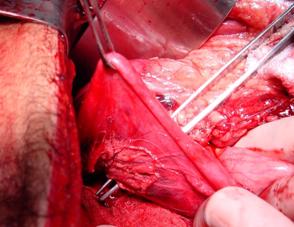

Plaga penetranta in regiunea precordiala Plaga penetranta in regiunea precordiala

Corp ascutit penetrat in regiunea precordiala Mediastin largit